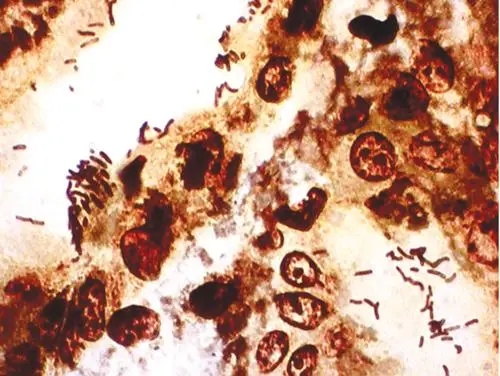

酵母菌镜检

酵母菌镜检 当前位置:首页 > 新利(中国) > 产品服务 > 瑞果产品展示 > 细菌